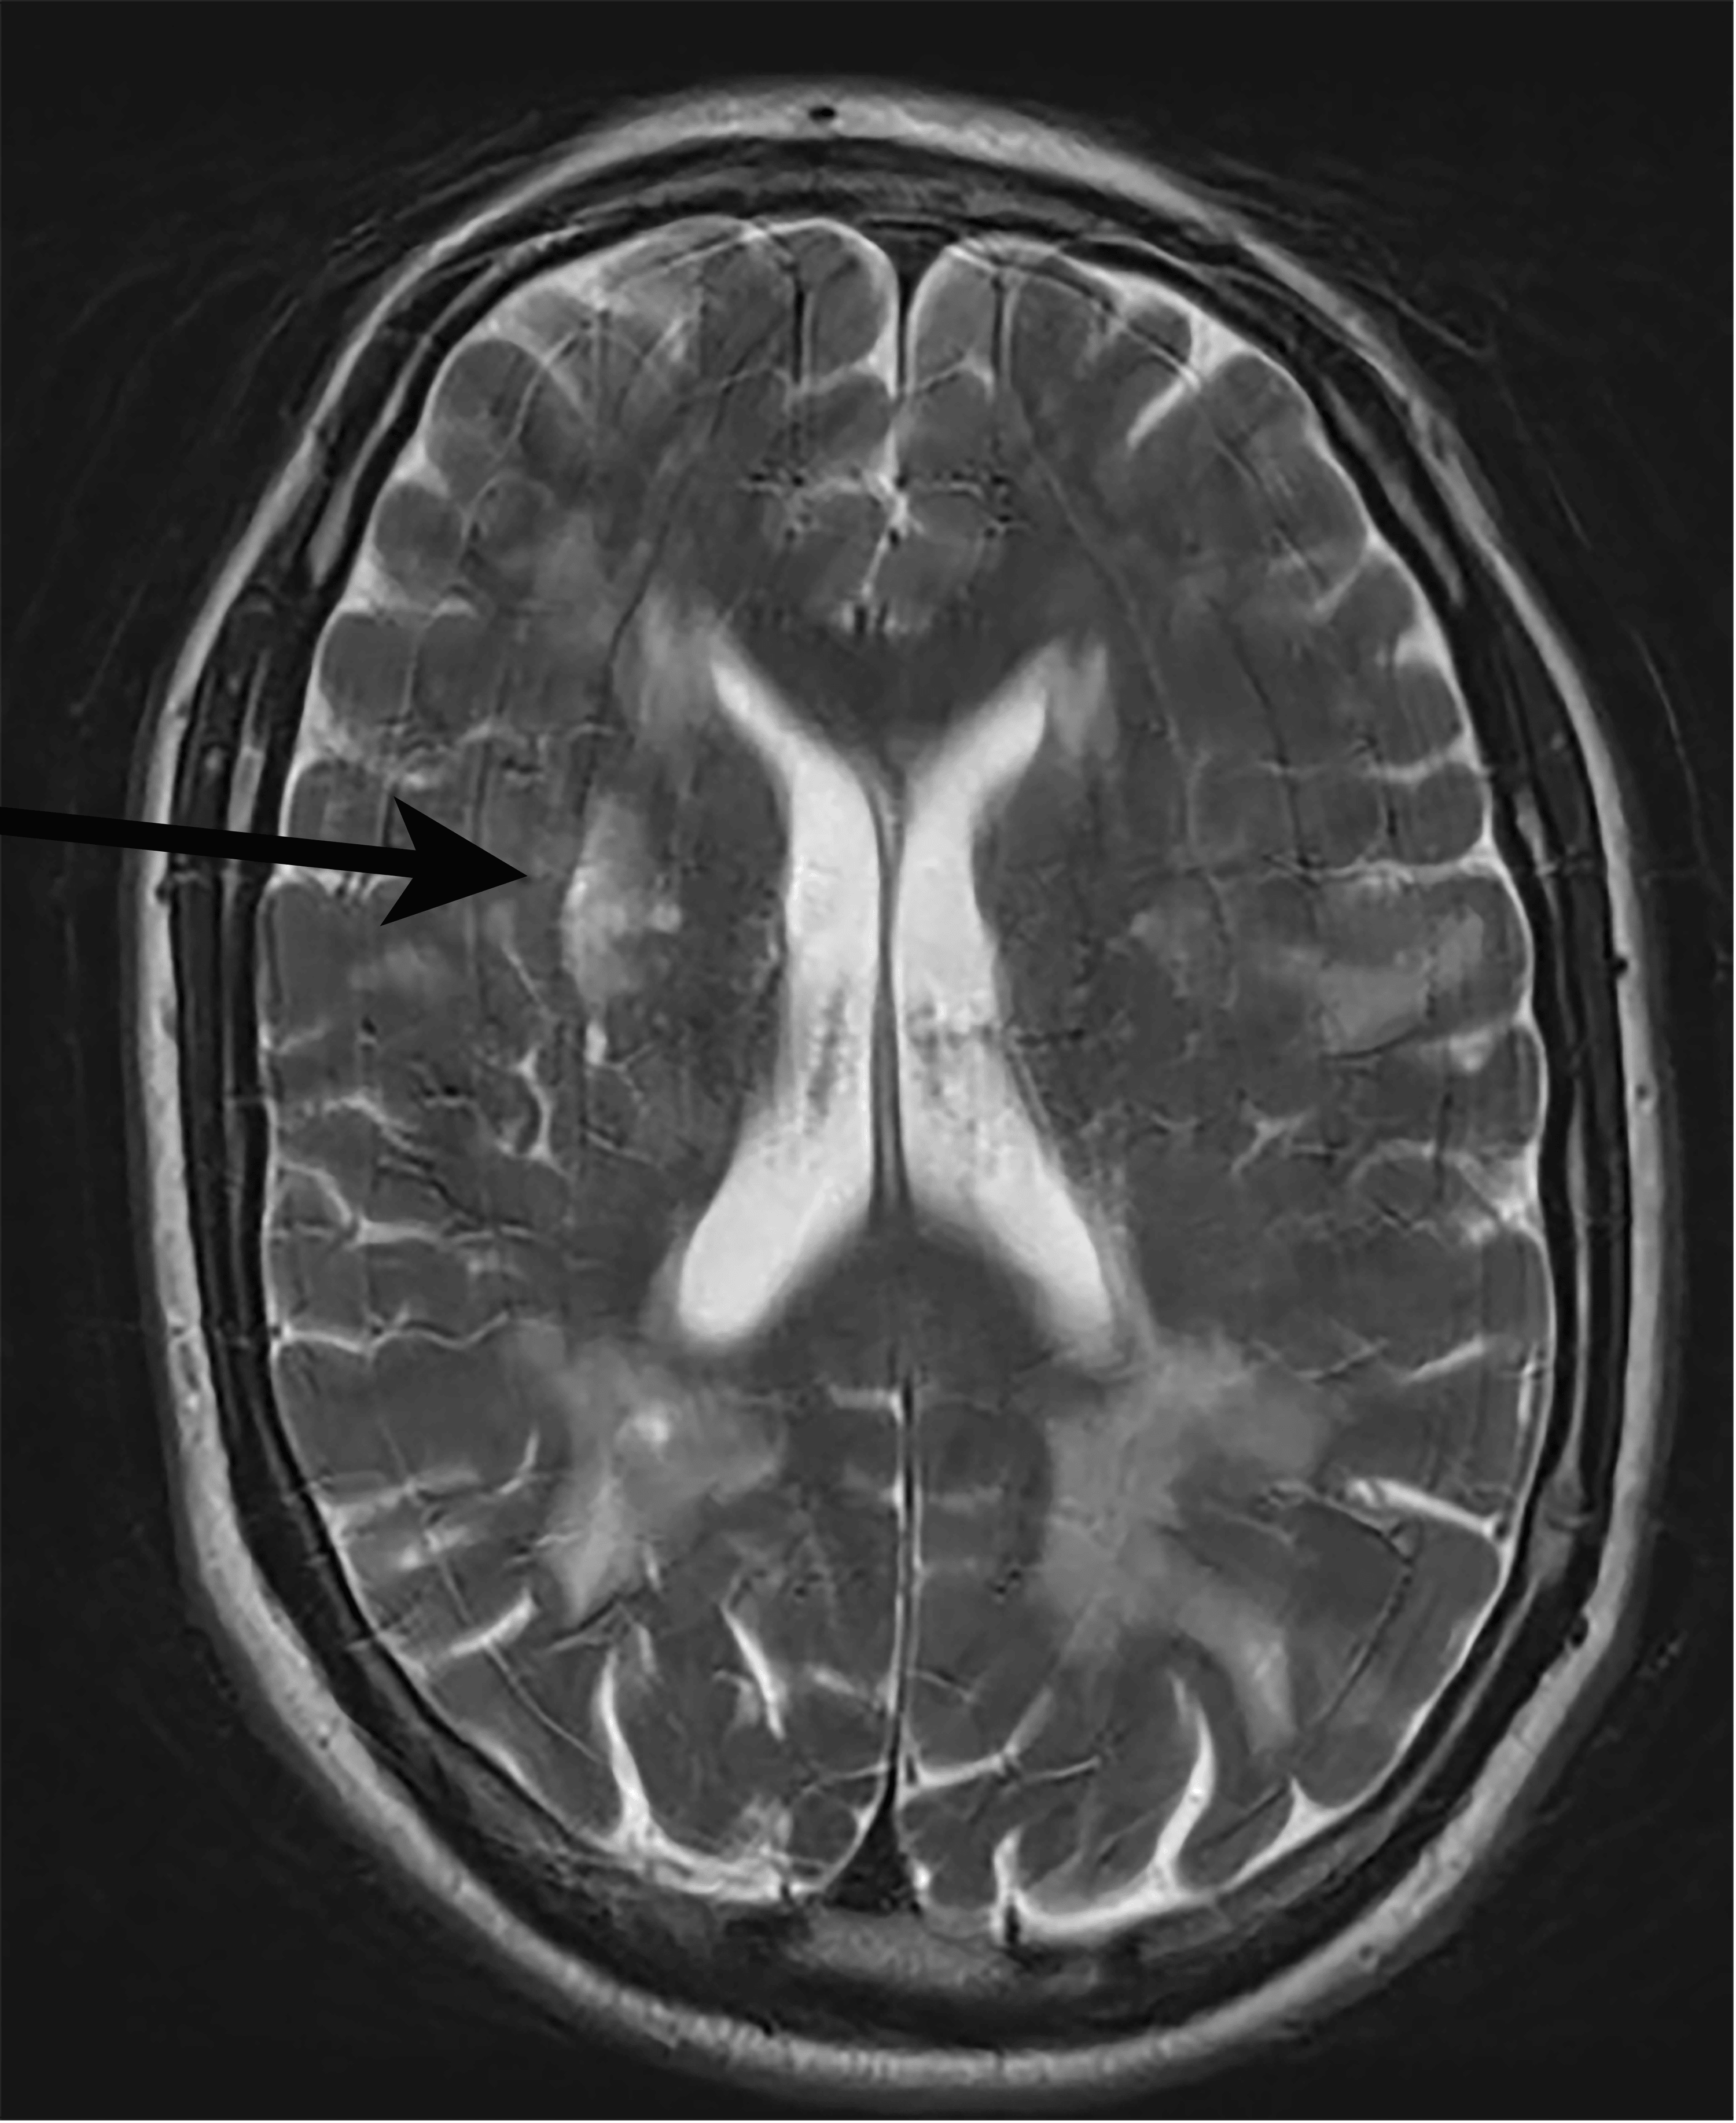

From www.researchgate.net

T2weighted MRI head imaging was obtained at the time of our patient’s Mri Head Dangers A head mri can help determine whether you sustained any damage from a stroke or head injury. You're allergic to the contrast dye. Because radiation is not used, there is no risk of exposure to radiation during an mri procedure. A brain mri, also called a head mri, uses a powerful magnetic field, radio waves and a computer to produce. Mri Head Dangers.